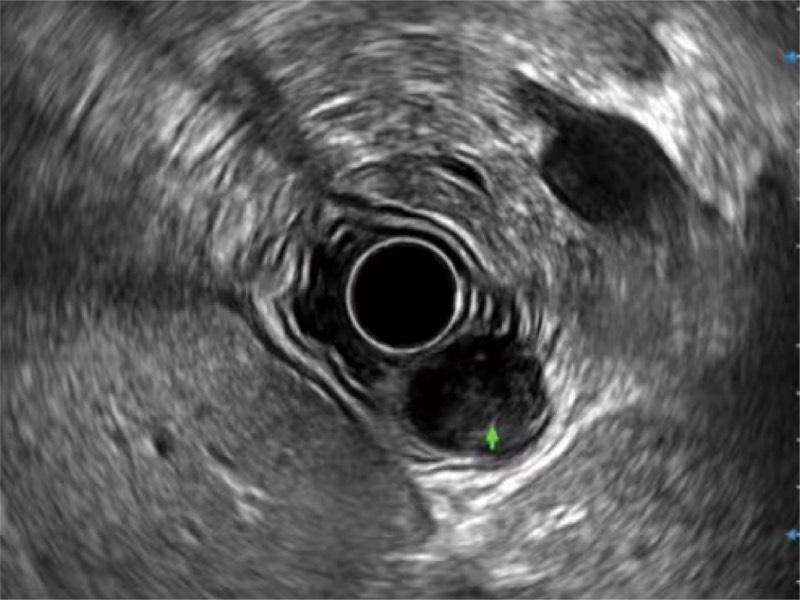

食管内间质瘤清晰显像

肝左叶和肝静脉的横截面